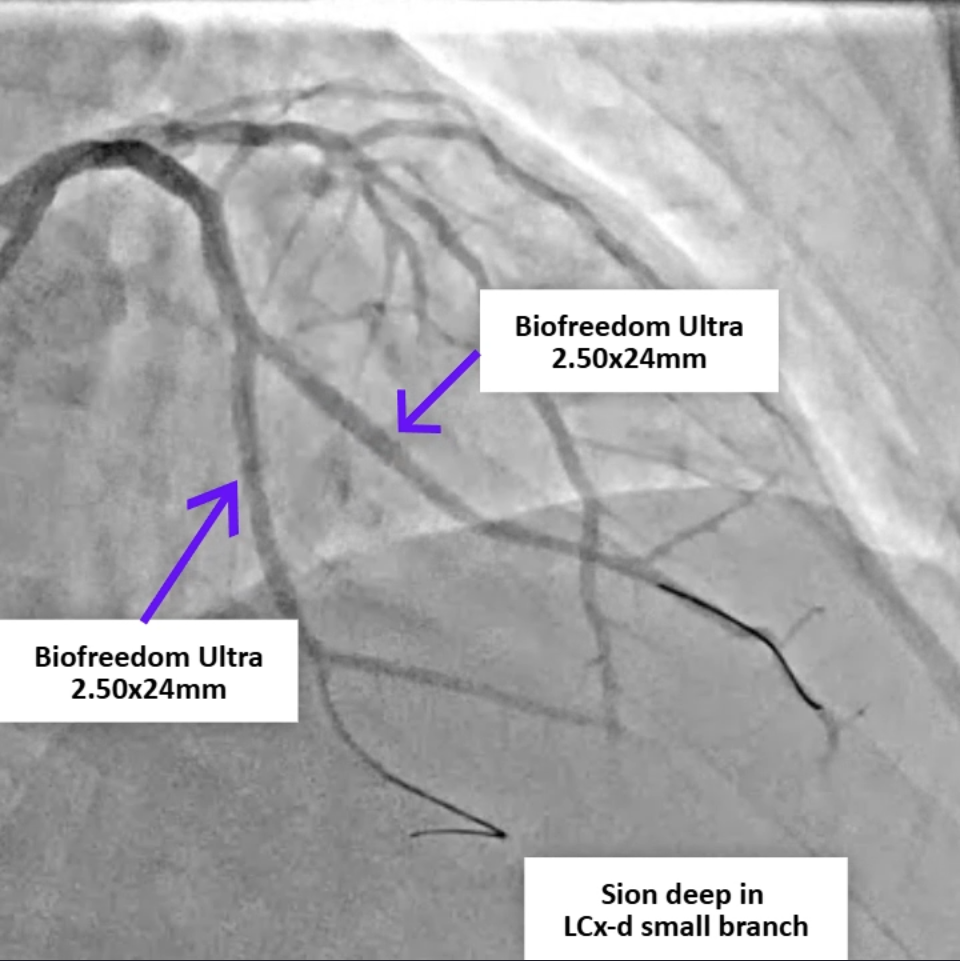

A 77-year-old man with hypertension, diabetes, and prior coronary artery disease presented with progressively typical angina for several days and was diagnosed with non-ST-elevation myocardial infarction. He underwent successful percutaneous coronary intervention with drug-eluting stents to the distal left circumflex and obtuse marginal (OM-1) branch, achieving TIMI-3 flow. Eight hours later, he developed sudden dizziness, diaphoresis, hypotension, and jugular venous distention.

Relevant Catheterization Findings

Review of the primary PCI angiography revealed no contrast extravasation; however, the Sion wire had advanced deeply into a small distal branch of the LCx artery, in hindsight possibly causing a distal micro-perforation. Repeat angiography demonstrated patent stents in both the left circumflex and obtuse marginal branches without in-stent thrombosis. No persistent or visible extravasation was noted, suggesting spontaneous hemostasis of the suspected micro-perforation.